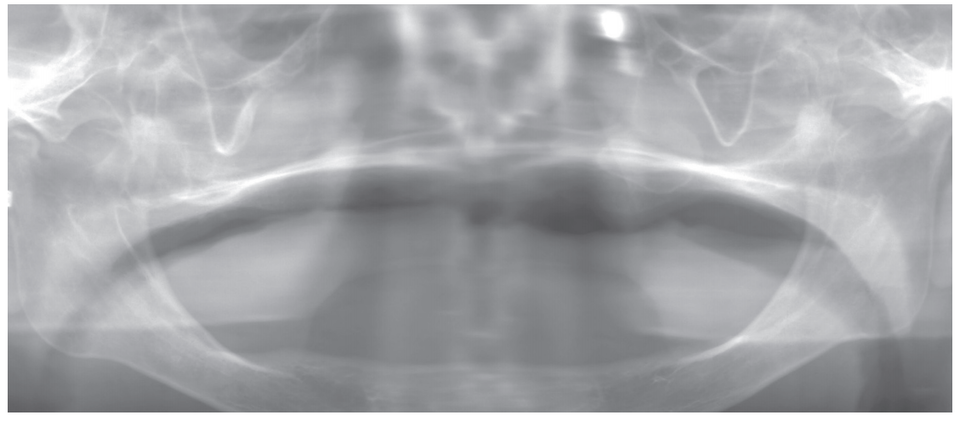

(2) 하악

하악 치조제 상부는 수평적 치조골흡수가 많이 진행되어 거의 수평 상태이다.

하악에 남아 있는 치조제 상태가 너무 열악하고, 하악 틀니 유지력에 도움을 주는 설하주름이 없다.

인상면에 중요한 지지 기반인 부착치은 면적이 부족하다.

후악설골근와를 손가락으로 촉지했을 때 설측으로 확장시킬 수 있는 공간이 부족하다. Retromolar pad 형태가 왜소하다.